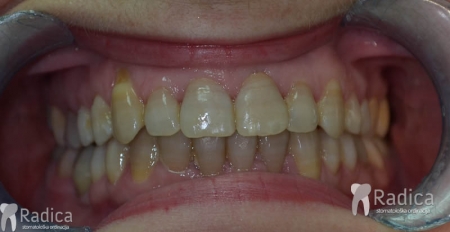

U galeriji slika su prikazani klinički slučajevi ovakvih odraslih pacijenta bilo da se radi samo o ortodontskoj terapiji ili predprotetskoj ortodonciji.

Kompresija –fiksni aparat bez ekstrakcije zuba

Slučaj 2